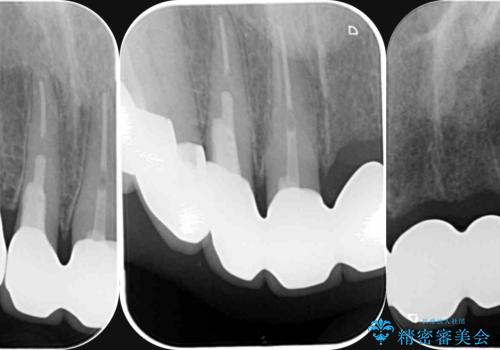

X線検査・視診より強くぶつけた前歯は折れてしまい、抜歯が必要な状況です。

元々の噛み合わせが深く(ディープバイト)、転んで顎を強打したことで上顎前歯2本が根元から折れてしまい抜歯をしなければいけない状況となってしまいました。